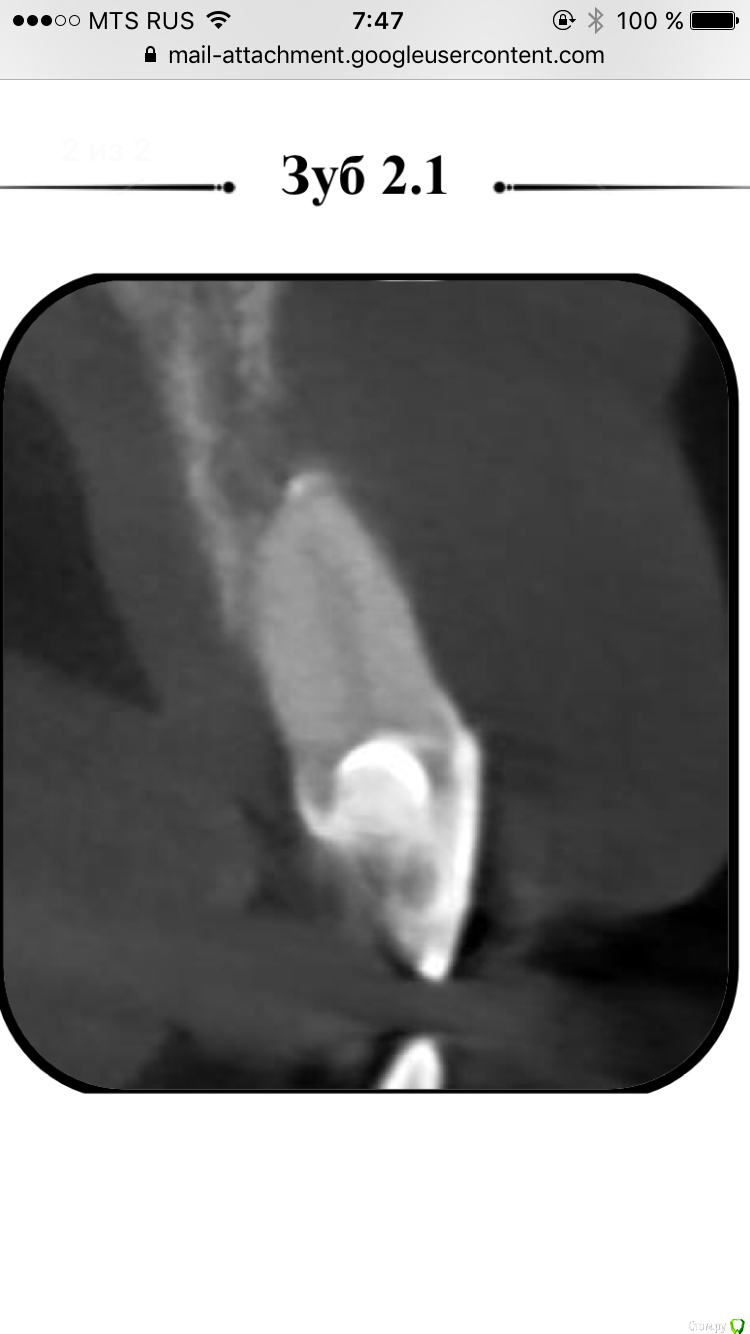

alina39 Опубликовано 9 декабря, 2016 Автор Поделиться Опубликовано 9 декабря, 2016 (изменено) Сделали новую КТ, подтвердился диагноз кистогранулема, почти киста по размерам.В прикрепленных - скриншот кт зуба.А главное боль не проходит, промыли и кальций положили неделю назад а боль не унимается, болит как рана и изредка дергает немного.Был один светлый период - 3 недели назад - когда зуб открыли, сказали полоскать и он неделю после этого не болел совсем, а потом все по новой. Изменено 9 декабря, 2016 пользователем alina39 Ссылка на комментарий

alina39 Опубликовано 9 декабря, 2016 Автор Поделиться Опубликовано 9 декабря, 2016 (изменено) покажите снимки на стадии леченияДругих снимков нет, сначала делали рентген, но на нем кисты не было видно, и потом вот два КТ: первый скриншот - это КТ 3 дня назад, а два других - 3 недели назад. Изменилось ли что-то за эти 3 недели? Изменено 9 декабря, 2016 пользователем alina39 Ссылка на комментарий